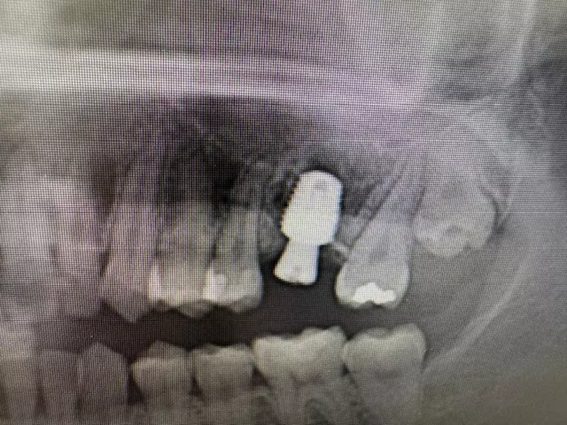

| 主訴 | 左上6番部 抜歯即時インプラント埋入。 |

| 治療内容 | 左上6番部インプラント埋入。 歯根破折により要抜歯。 抜歯即時埋入。 上顎洞まで1.5㎜。 |